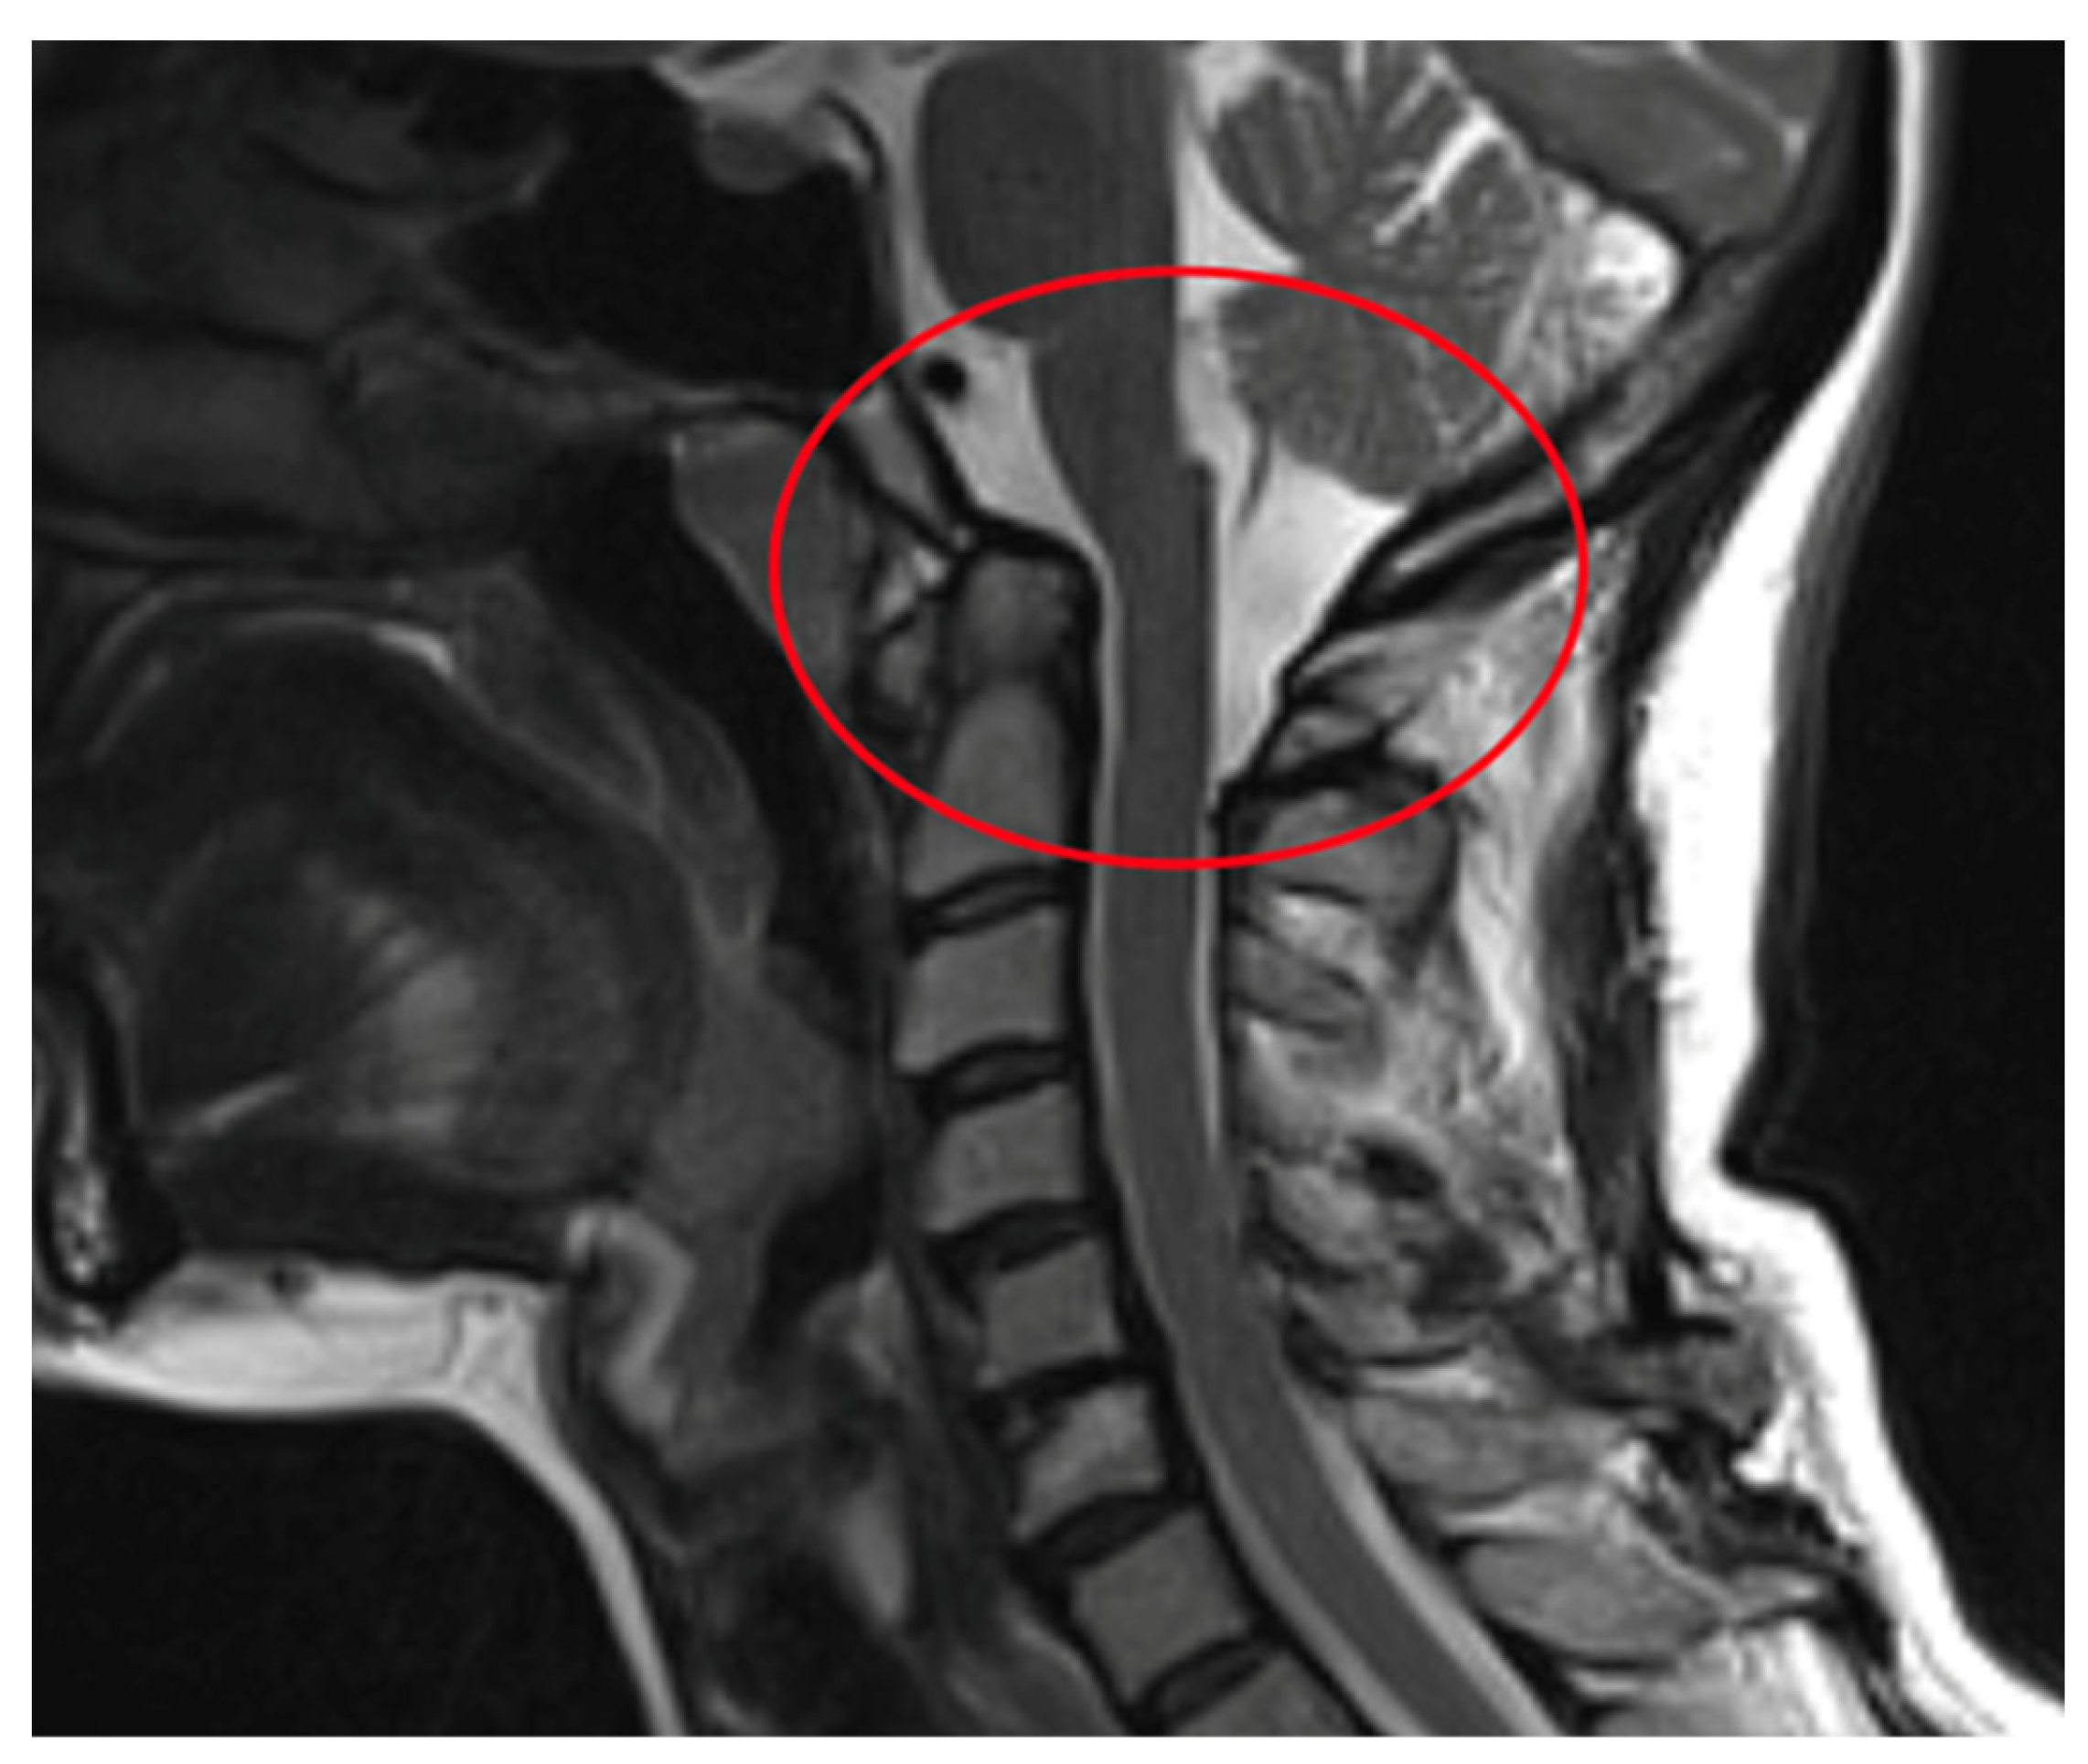

| AAS (atlantoaxial subluxation) | Weakening or rupture of ligaments and subchondral bone erosion in the atlantoaxial C1–C2 joints. |

| SAS (subaxial subluxation) | Subluxation in the joints C2–C7 due to destruction of the joint surface and the ligaments between the processes spinosis. |

| CS (cranial settling) | Vertical translocation of dens C0–C2 into the foramen magnum. |